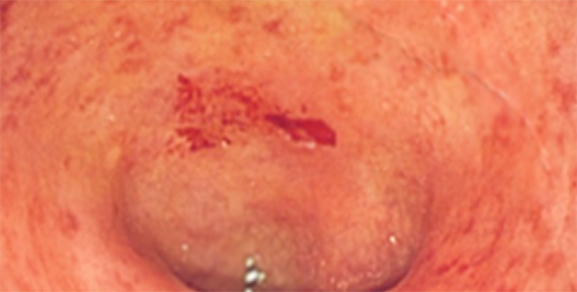

궤양성 대장염 초기 2) 궤양성 대장염의 증상?

가장 흔한 증상은 혈변이며, 6주 이상의 무른변(만성 설사), 대변 절박증, 후중감, 점액변, 야간설사, 경련복통, 배변 전 좌하복부 통증 및 불쾌감 등이 동반됩니다.

증상이 진행되면 식욕부진, 오심, 구역, 구토, 발열, 부종 전신쇠약감등이 동반될 수 있습니다.